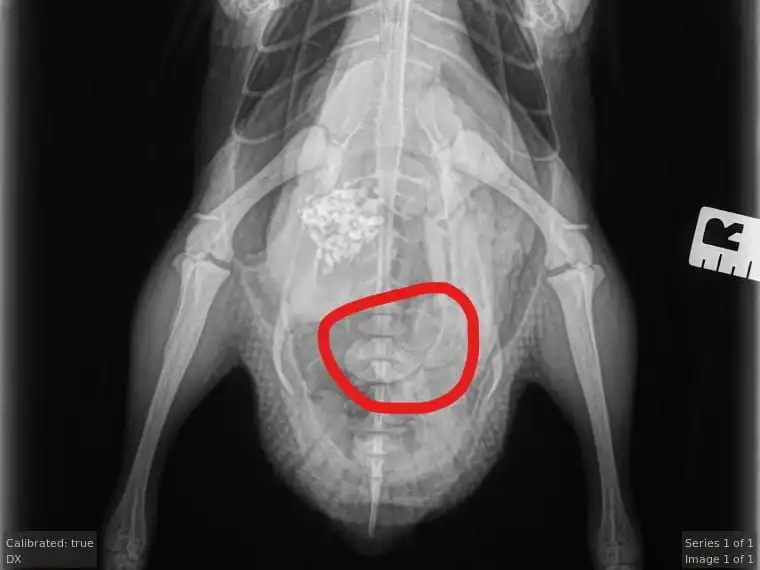

Egg binding, or dystocia, is a common problem in domestic ducks. It occurs when a duck cannot pass an egg that has been formed, either due to a physical obstruction or a lack of muscle tone in the reproductive tract. This can be a serious issue for ducks, leading to infection, injury, and even death if left untreated.

Several signs indicate that a duck may be egg-bound. These include a swollen abdomen, lethargy, a lack of appetite, and straining to lay an egg without success. Sometimes, a duck may also show signs of pain or discomfort. Below is a comprehensive list of possible symptoms:

If you suspect a duck is egg-bound, seeking veterinary care as soon as possible is important. The egg could block feces from getting released. Your duck can die within 24 hours if this happens. So check to see if your duck still poops.

In some cases, physical obstructions within the reproductive tract can impede the passage of eggs, leading to egg binding. Tumors, cysts, or other abnormalities may obstruct the oviduct, preventing the egg from progressing along its natural path. These obstructions can pose significant challenges and may require veterinary intervention to resolve.

Surgical Intervention

However, surgical intervention may be necessary if the egg binding in your duck is caused by a physical obstruction within the reproductive tract. A skilled avian veterinarian can perform a surgical procedure to remove the obstruction, whether a tumor, cyst, or other anatomical anomaly, allowing the egg to be safely expelled. Surgery may also be required to repair any damage to the reproductive organs caused by the obstruction or prolonged egg retention.